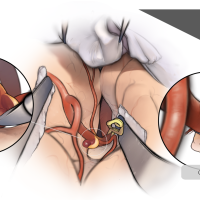

術後イラストシリーズ

監修:太田 仲郎